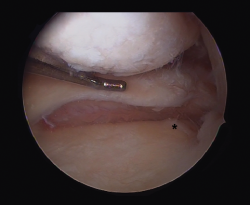

Meniscal root lesions

Meniscal root lesions are lesions located at less than 1 cm from the bone insertion of the meniscus, or lesions that involve bone avulsion of the anchoring zone (Figure 4). While lesions of the posterior root of the medial meniscus are related to degenerative processes, lesions of the posterior root of the external meniscus are associated to lesions of the ACL (7-12%)(30). Rupture of the posterior root of the medial meniscus biomechanically behaves like a total meniscectomy(31), while rupture of the posterior root of the external meniscus associated to ACL rupture results in an increase in anterior translation of the tibia and adds increased rotational instability, incrementing pivot shift(32).

Figure 4. Rupture of the posterior root of the medial meniscus. Note the lack of continuity in the posterior horn of the medial meniscus, exhibiting a space between the root and its insertion imprint in the tibia (*). Left knee; view from the anterolateral port.